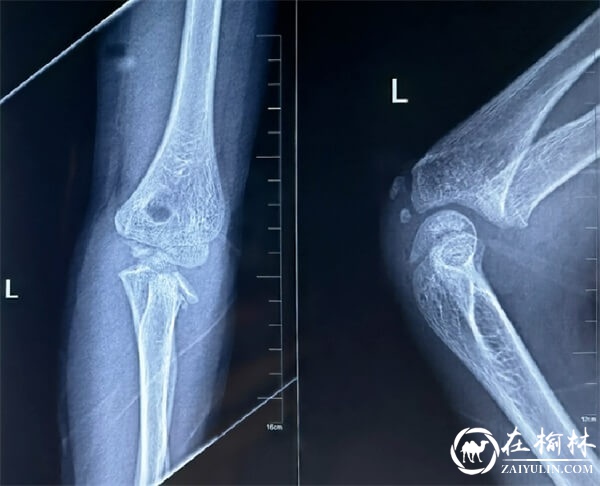

3月15日,骨科医院李勇副主任医师接收了一名年仅10岁的外伤患儿,患者入院后诊断为:左侧桡骨颈骨折。经高智主任医师团队讨论后一致认为,该患儿桡骨颈骨折为Judet分型4型,手法复位困难,不能达到满意的效果。反复透视下克氏针撬拔复位,辐射大,容易损伤桡神经及其分支,切开复位固定容易损伤骨骺及创伤大。经讨论,考虑在超声引导下克氏针撬拨复位弹性髓内针内固定治疗此骨折,该方法极大的减少了X射线的辐射、减少了神经损伤风险,微创并且达到完美骨折复位效果。